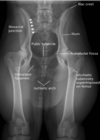

Review pelvic anatomy.

Extended VD pelvis view means..

the patellas are also in the image and they're rotated to position in the center of the femurs.

identify

VD flexed view “Frog position” Conscious patient with painful hips. Cranial and caudal aspect of femoral head and neck should be visible.